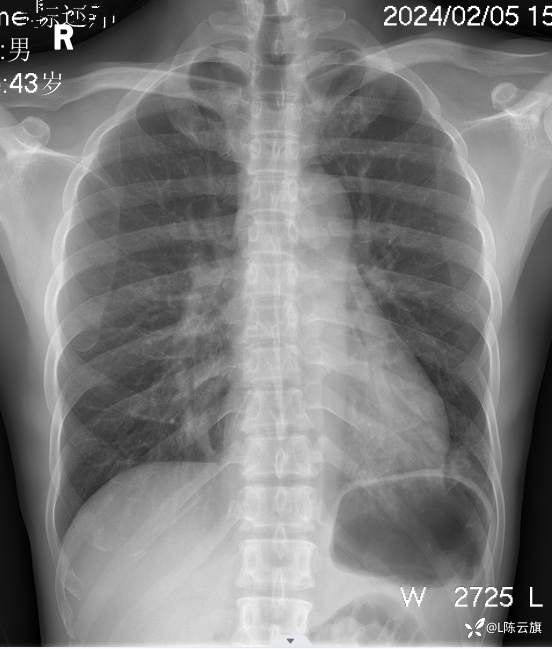

胸片4: